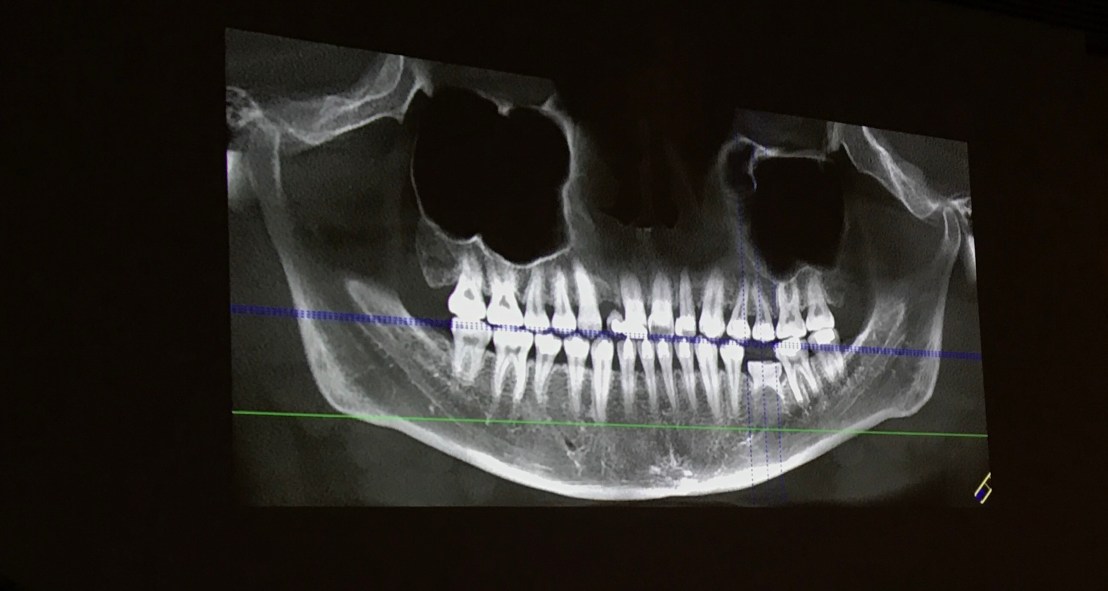

OPG

จะเห็นว่า แม้ฟันสึกมาก แต่กลับไม่ค่อยมีรอยโรคปลายรากครับ

ฟันสึกแต่ vital ทุกซี่ครับ

ภาพ OPG

OPG Final pros